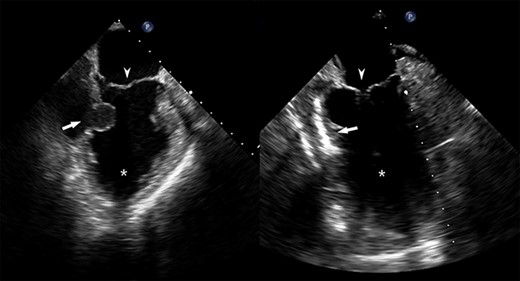

He returned 5 weeks later complaining of 72 hours of malaise, fevers and chest pressure. He was tachycardic and hypotensive but intermittently responsive to fluid resuscitation. He noted reluctance to present for evaluation, given concerns regarding COVID-19 exposure if he was hospitalized. A computed tomography (CT) of the chest noted a left ventricular irregularity and adjacent thrombus (Fig. 1). Echocardiography revealed an ejection fraction of 35%, a large pericardial effusion and an aneurysmal-appearing inferolateral left ventricular wall with intrapericardial thrombus (Fig. 2).

Coronal CT demonstrating left ventricular wall defect and intrapericardial thrombus; asterisk = left ventricular cavity, arrow = left ventricle free wall defect, arrowhead = thrombus.